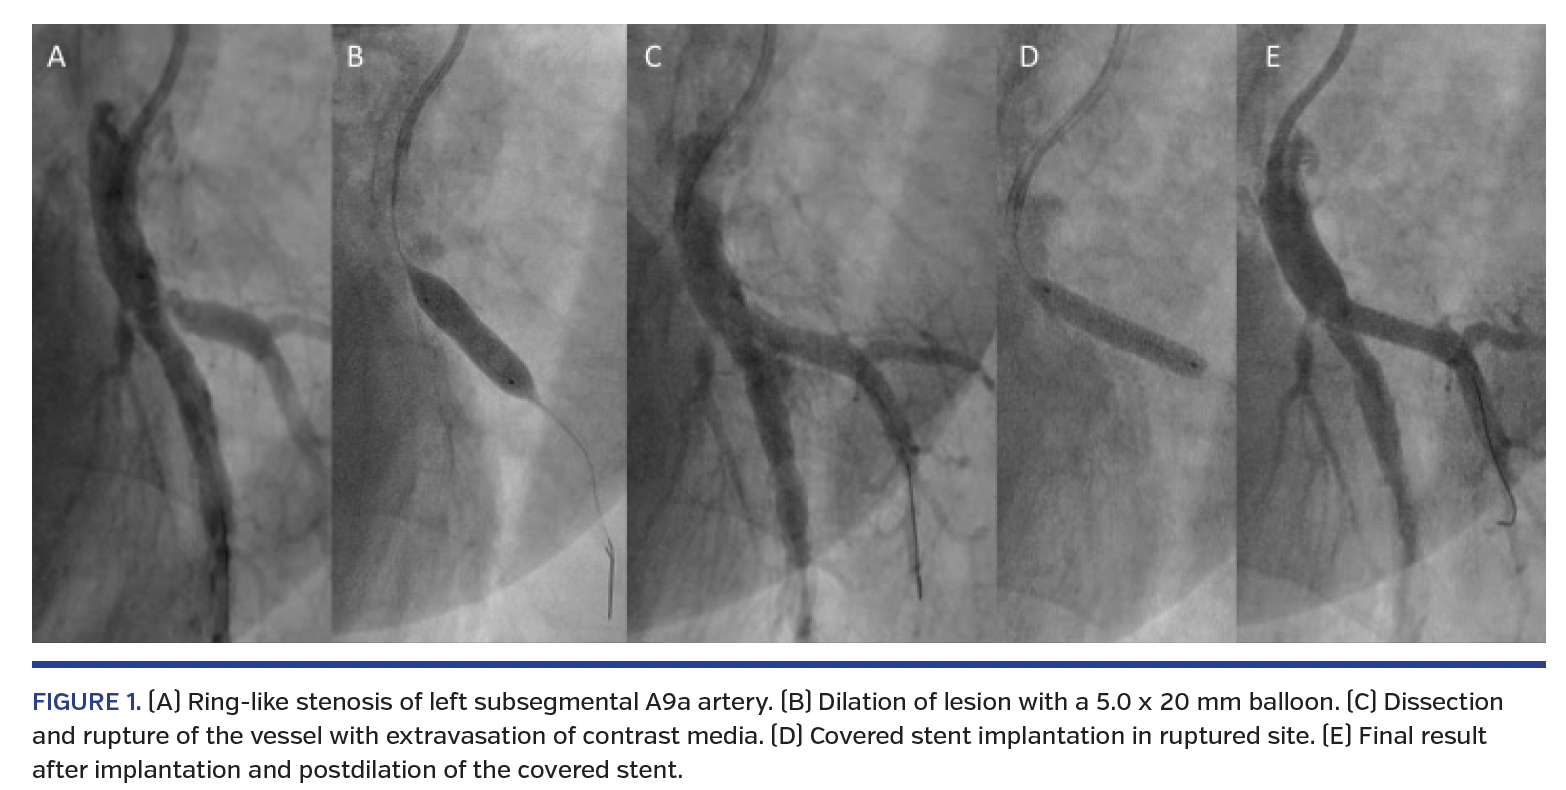

A 62-year-old female with residual pulmonary hypertension after pulmonary endarterectomy for chronic thromboembolic pulmonary hypertension (CTEPH) underwent balloon pulmonary angioplasty (BPA). At baseline, she was in functional class III and mean pulmonary artery pressure was 50 mm Hg. BPA was performed as a staged procedure; at the third BPA session, we targeted the left subsegmental A9a artery. Selective pulmonary angiography showed the ring-like lesion (Figure 1A). Subsequently, we dilated the lesion with a 5.0 x 20 mm Viatrac balloon (Abbott Vascular) (Figure 1B). However, immediately after deflation of the balloon, severe hemosputum and cough occurred. Pulmonary angiography showed extravasation of contrast medium (Figure 1C; Video 1) and pulmonary artery rupture and dissection were recognized. A 3.0 x 20 mm Jostent GraftMaster covered stent (Abbott Vascular) was implanted to the rupture site (Figure 1D). Control angiography revealed the disappearance of extravasation of contrast medium (Figure 1E; Video 2). Pulmonary computed tomography angiography performed 12 months later showed no signs of in-stent restenosis and patency of the vessel (Figures 1F, 1G). Three-dimensional reconstruction of the computed tomography pulmonary angiography is shown in Figure 1H.

The ring-like lesions in CTEPH patients are sometimes difficult to dilate because they are hard and fibrotic. For this reason, slightly oversized balloons are used. However, this may result in an increased risk of vessel rupture. Implantation of a covered stent not only protects the ruptured vessel, but also maintains perfusion in the future.